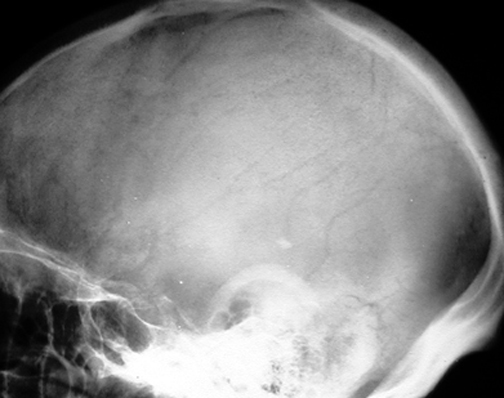

Identify the sutures seen. Click the image for labeling.